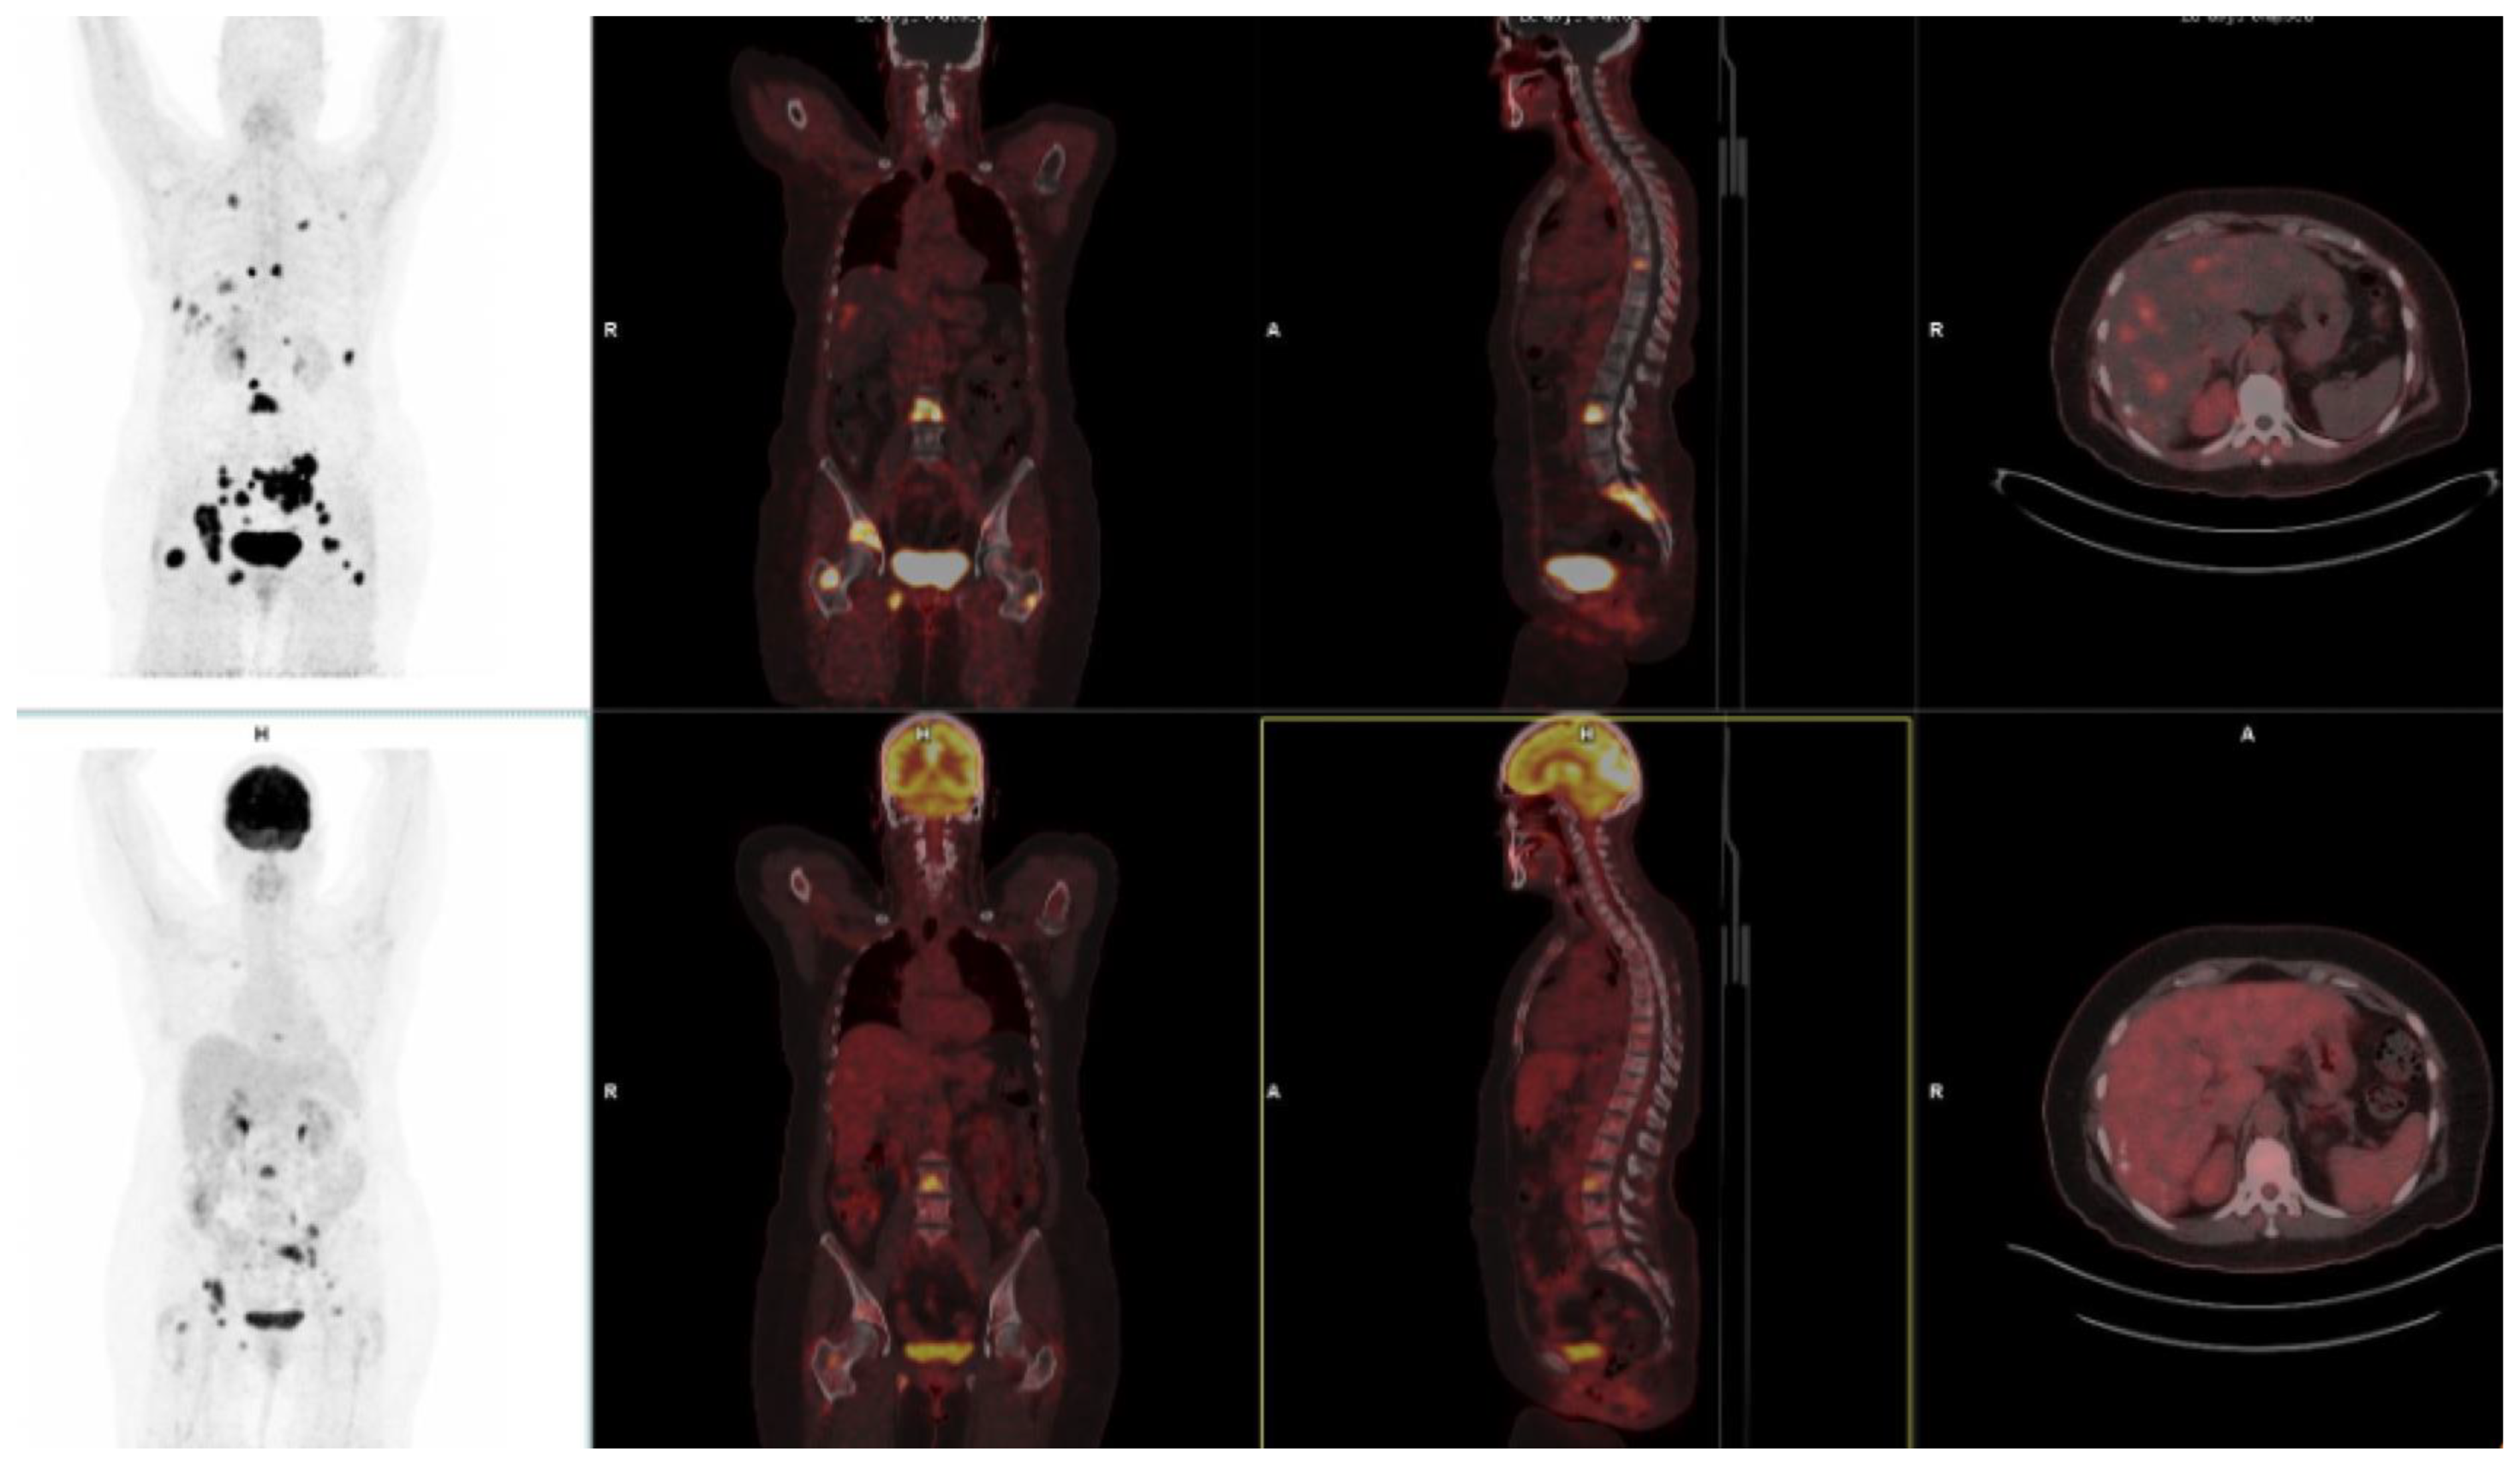

10. FAPI-Based Theranostic Approaches

11. Challenges and Limitations in FAPI Therapeutic Approaches

12. The Potential Role of FAPI PET-Based Theranostic Approaches